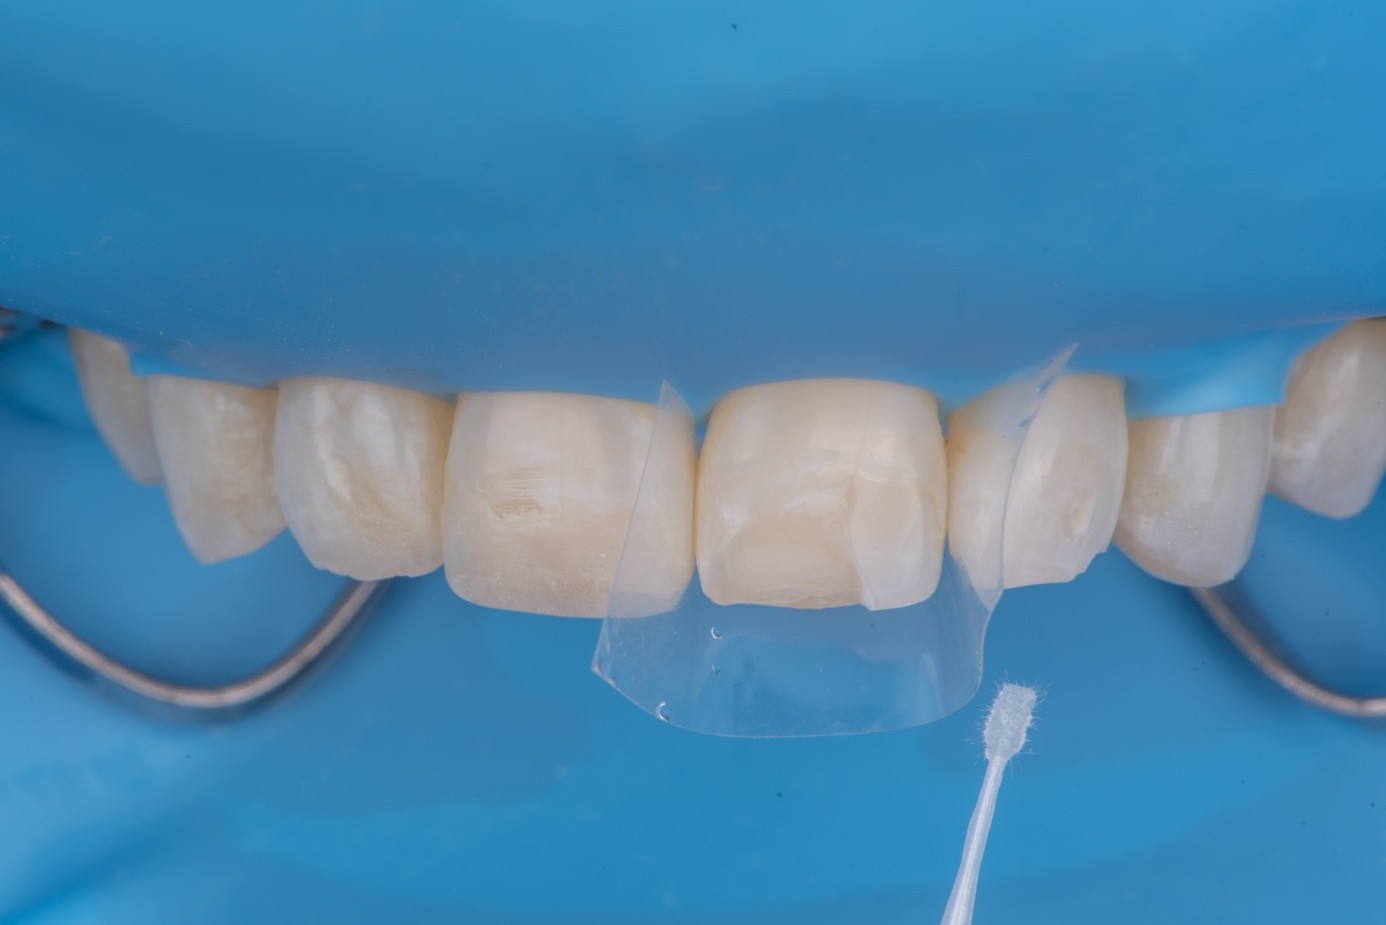

After shade selection and clinical photos, absolute isolation with a rubber dam was achieved. The intaglio surface of the fractured piece was air abraded with glass beads at 2 bars of pressure to remove residual cement. Aluminum oxide powder should be avoided on glass ceramics, as it tends to create microcracks and has shown to decrease bonding strength (Figure 4 and Figure 5).4 The fractured piece was etched with 9% hydrofluoric acid for 120 seconds followed by thorough rinsing for 20 seconds, then scrubbed with 37% phosphoric acid for 60 seconds and placed in an ultrasonic bath for four minutes in distilled water, rinsed, dried, and treated with silane to promote chemical bonding and heat treated at 100 °C for 5 seconds (Figure 6).5,6 The combination of the phosphoric acid scrub and the ultrasonic bath after HF etching helps to remove any calcium salt residues created during HF etching.

On the tooth side, exposed dentin was protected with a liquid dam (OpalDam, Ultradent) during ceramic conditioning to prevent HF contamination and maintain bond strength and scrubbed with phosphoric acid and rinsed and dried (in a similar manner as the fractured piece), and silane applied (Figure 7 through Figure 9). After surface cleaning, the tooth surface was air abraded with 30-micron aluminum oxide (RONDOflex, KaVo) with care taken not to air abrade the ceramic, then primed with adhesive using OptiBond FL (Kerr Dental) following manufacturer’s recommendations (Figure 10).

(7.) Protection of adjacent teeth and the dentin tissue during surface treatment of the fractured ceramic margin.

Figure 7

(8.) Protection of adjacent teeth and the dentin tissue during surface treatment of the fractured ceramic margin.

Figure 8

(9.) Protection of adjacent teeth and the dentin tissue during surface treatment of the fractured ceramic margin.

Figure 9

(10.) Application of adhesive onto the prepared tooth substrate prior to reattachment of the fractured ceramic fragment.

Figure 10